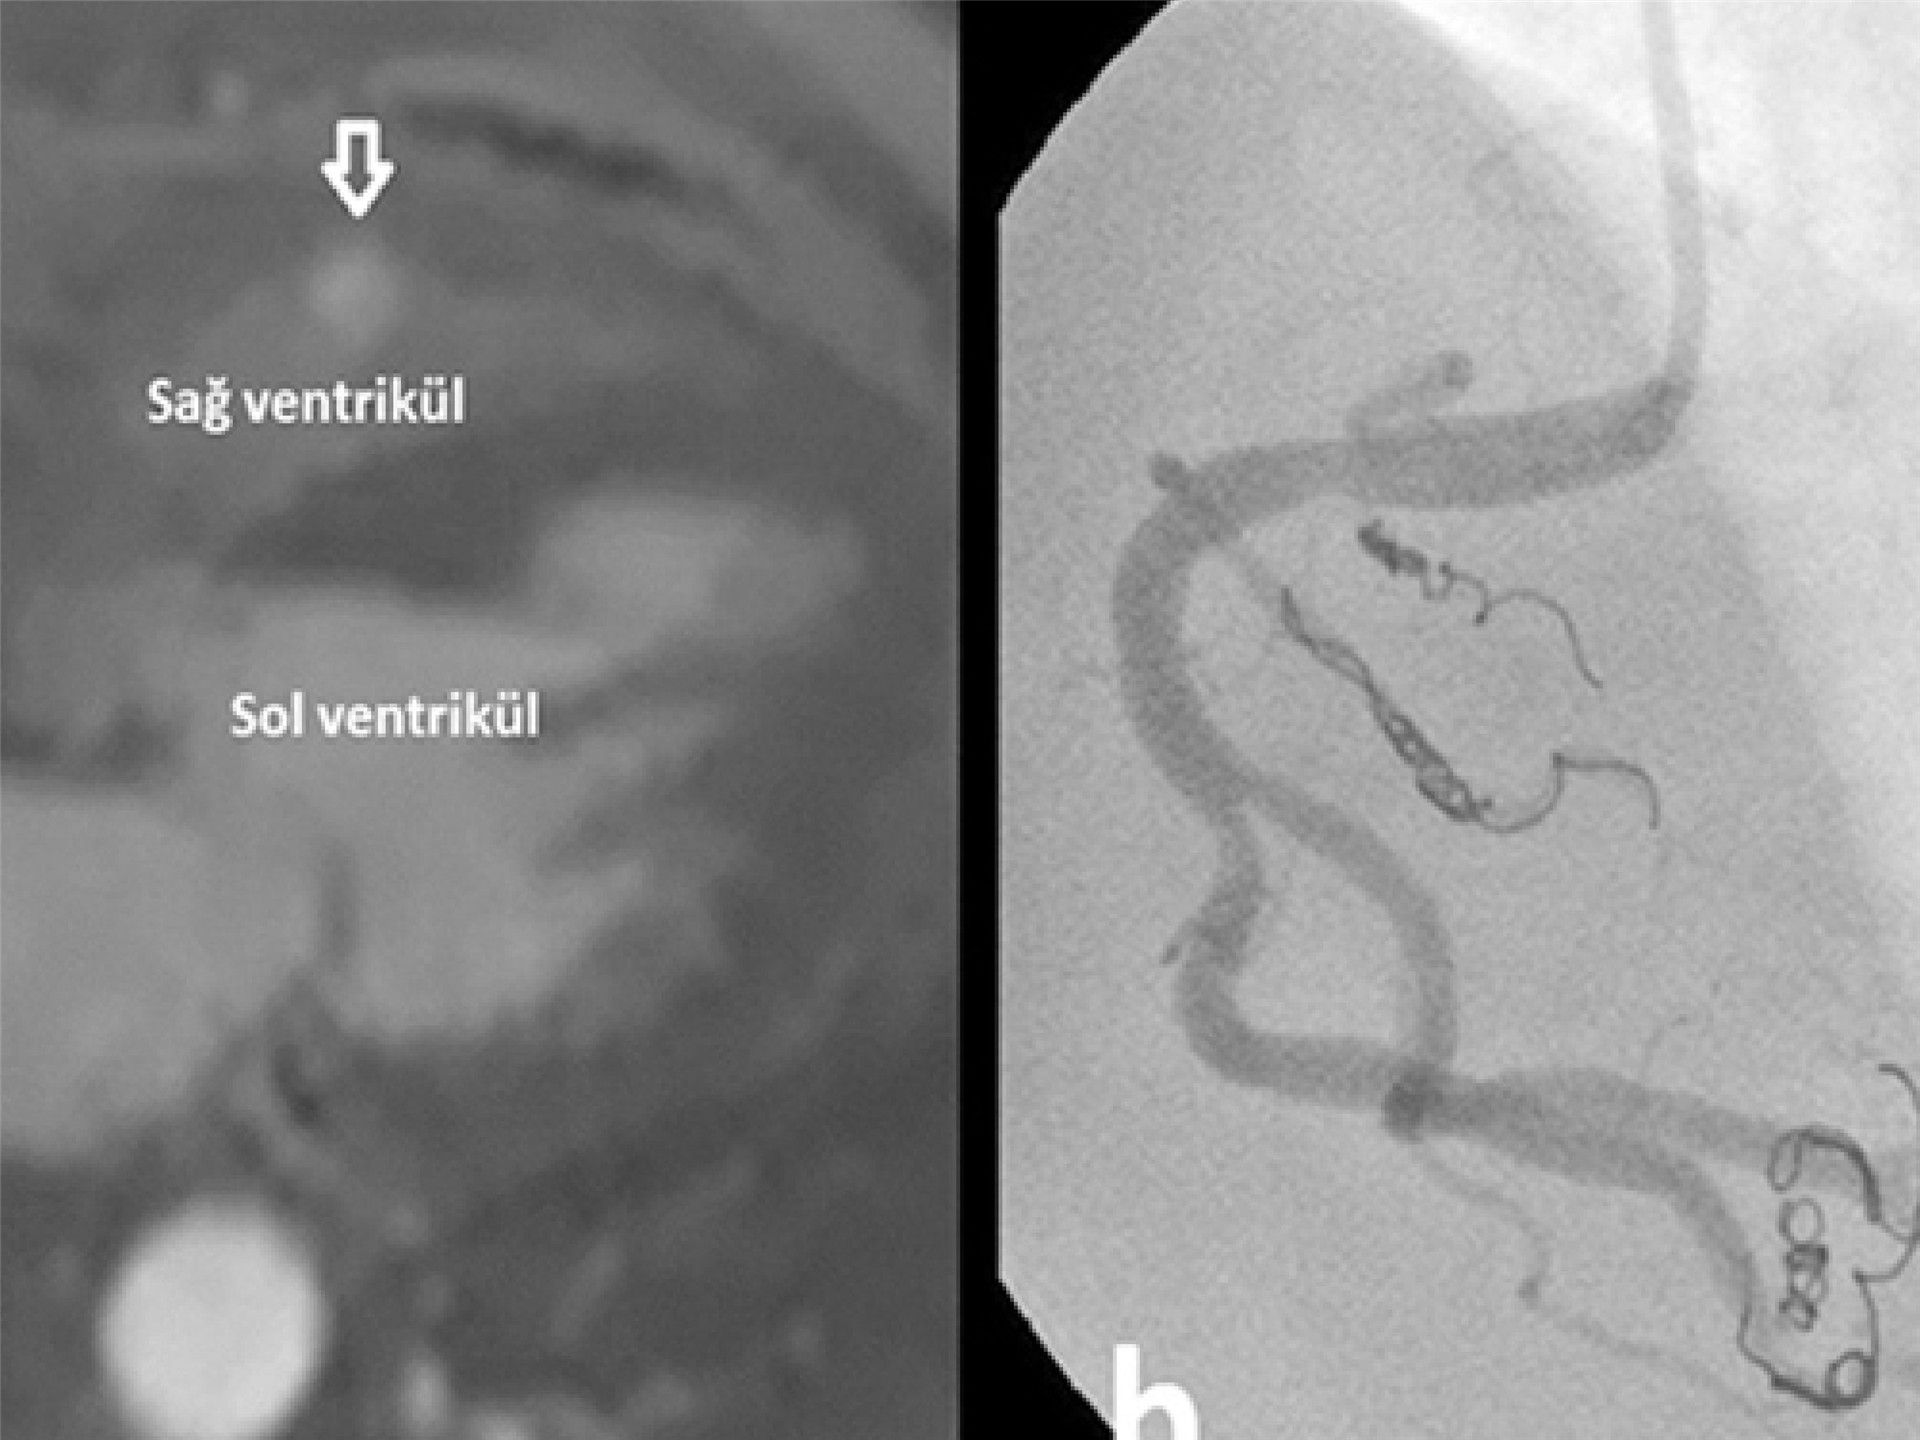

Embolizasyon, damar içerisindeki anormal bağlantıyı veya kan akışını kontrollü şekilde kapatmayı amaçlayan minimal invaziv bir tedavi yöntemidir. Bu işlem sırasında özel kateterler ve embolik materyaller kullanılarak fistül veya problemli damar bölgesi kapatılır.

• Embolik coil sistemleri

• Vasküler tıkaç cihazları